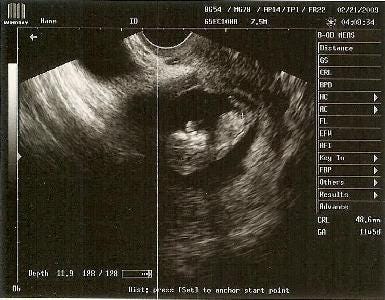

This doesn’t mean that people shouldn’t talk about the kids they’re having. Far from it; I’m delighted every time I hear that my arguments have created a life. What it means, rather, is that one should follow the rule, “Don’t ask, do tell.” You should avoid asking sensitive personal questions, but there’s every reason to share happy personal information. Such as… another Caplan baby is on the way!

No joke! Starting mid-September, I’ll be expecting another baby, and EconLog readers should be expecting a lot of 2 AM posts.